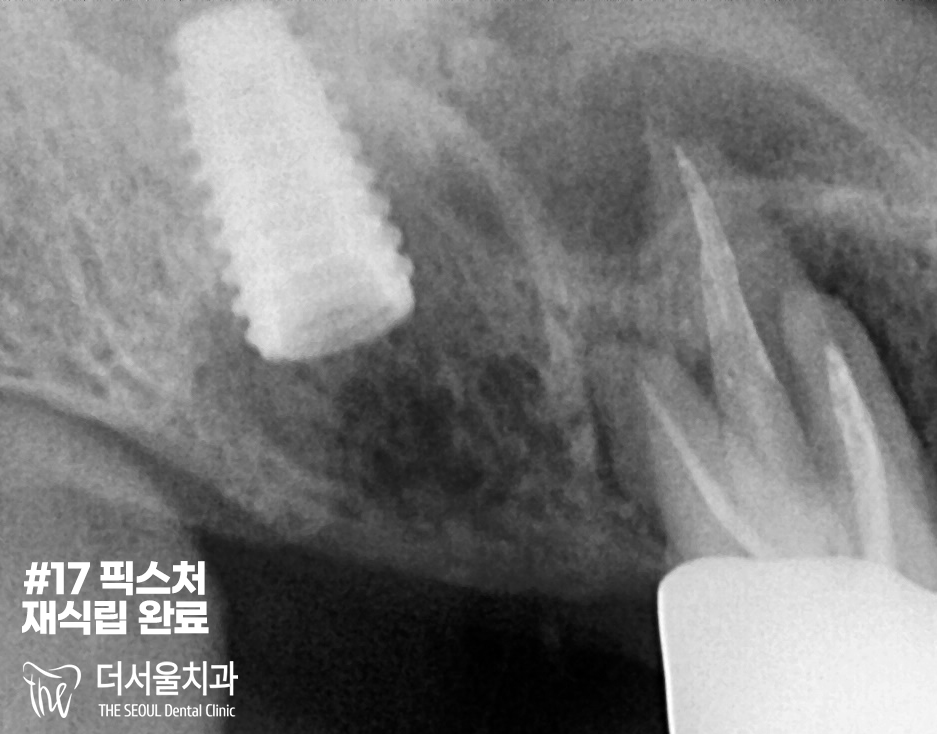

『수술 완료』

하얗게 채워져있는 골이식 재료가

뼈와 결합이 잘 이뤄진 것을 확인할 수 있습니다.

2개를 심지 않으면 파절될 수 있다는

사항을 알려드렸음에도

환자분께서는 하나만 하기를

요청하셨기에 해드렸습니다.

『재수술』

재수술이기에 서현역치과 의료진은

좀 더 신경써서 픽스처를 심었습니다.